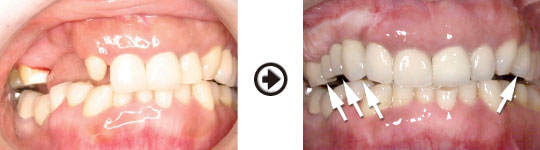

インプラント治療(GBR)過程

骨幅が無い所でも骨造成することでインプラント治療が可能になります。